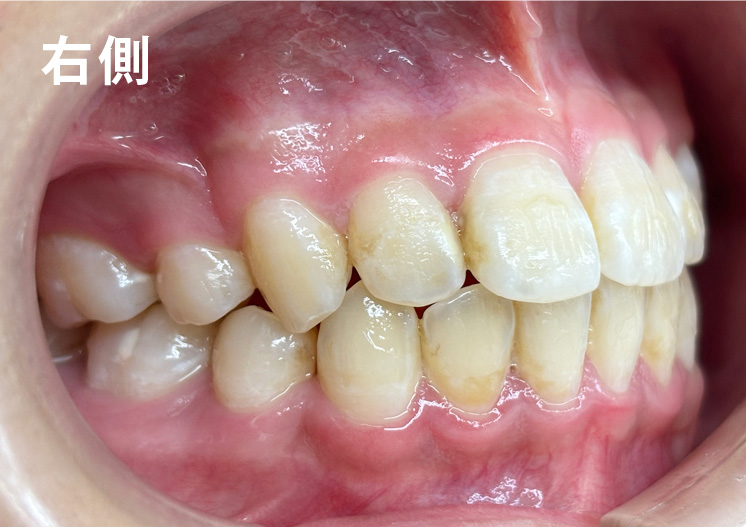

矯正bofore

矯正種類 ワイヤー矯正

症例 上下額叢生

治療期間 2021年12月〜2024年10月

性別/年代 男 13歳

治療費 748,000円

適切な時期に治療が開始できたので、歯並びだけでなく顎や顔貌も理想的に成長しました。歯磨きもしっかりできるようになりました。